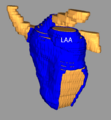

- Carma norm LAA.png 591 × 591; 98 KB

- Carma vert LAA.png 579 × 626; 148 KB